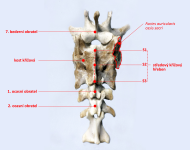

páteř psa a možné lokalizace přechodového obratle

páteř psa a možné lokalizace přechodového obratle

Křížová kost

Křížová kost

Křížová kost se sousedními obratli

Křížová kost se sousedními obratli

Srovnání zdravé křížové kosti a nejnižšího typu vady

Srovnání zdravé křížové kosti a nejnižšího typu vady